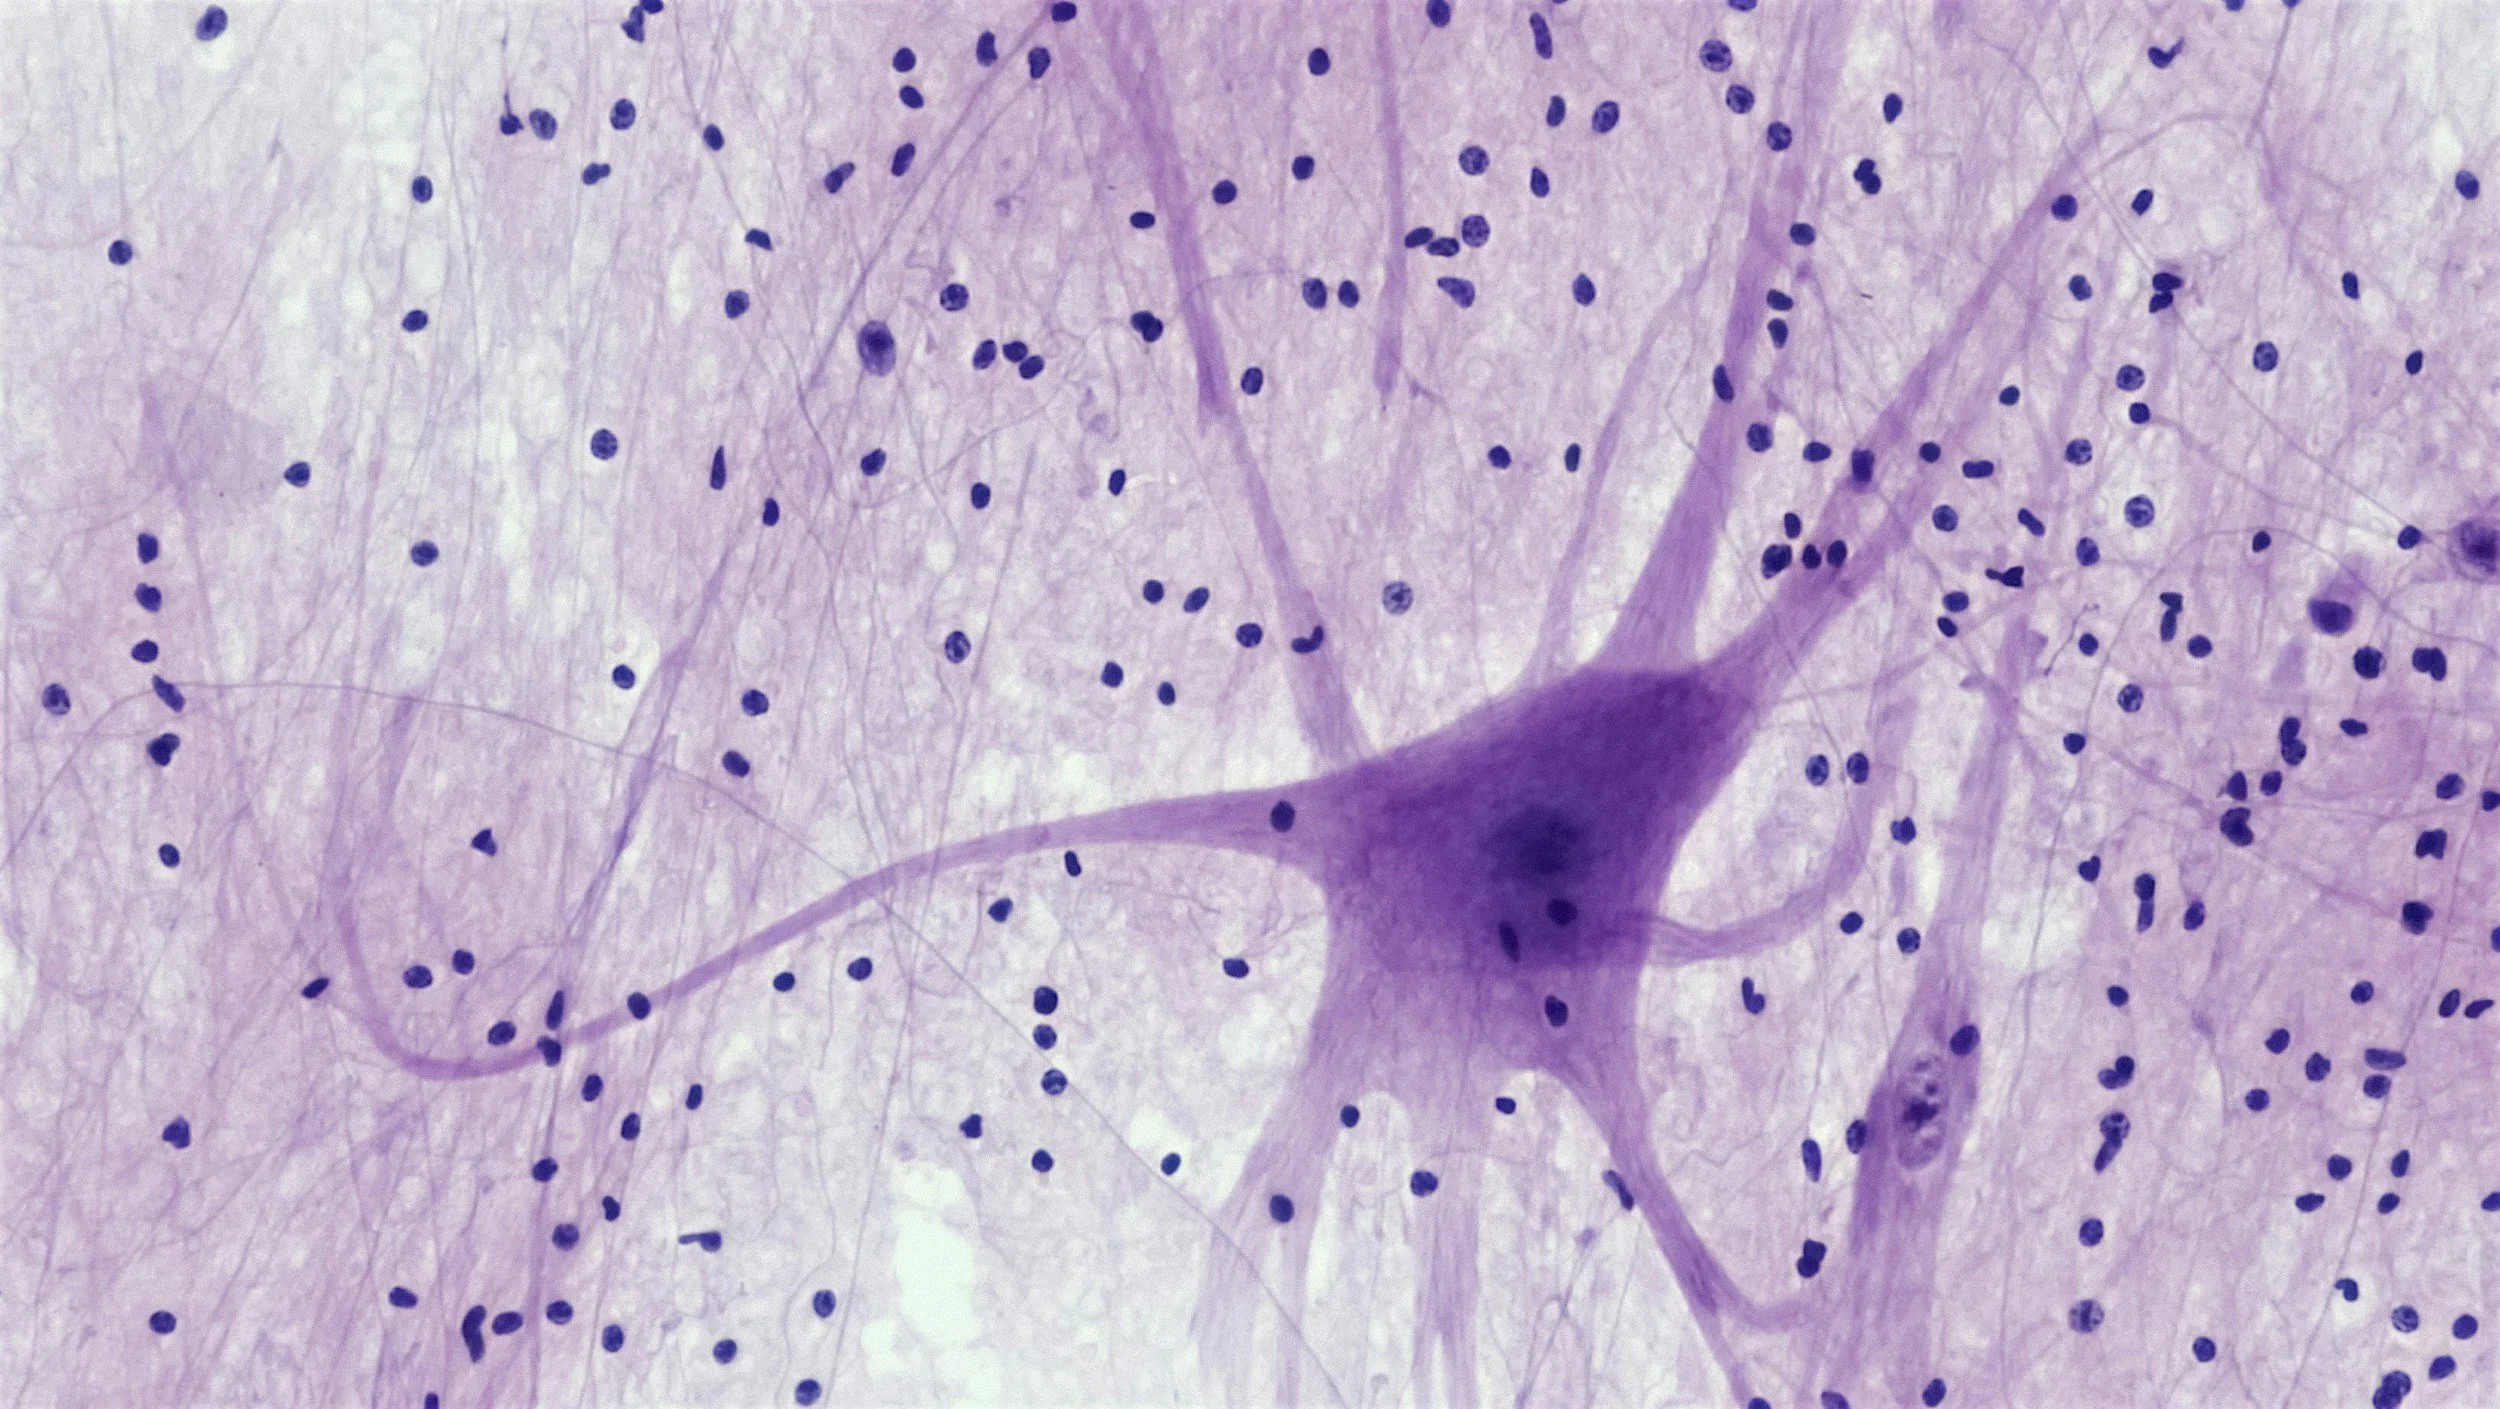

Polyvagal theory for kids

In Early Childhood Education, we often use tools such as The Colour Monster and Zones of Regulation to help children understand their feelings and emotions. To deepen those understandings, we can use The Polyvagal Theory to begin to explore where these feelings don’t exist in isolation - that they are impacted by our nervous system, something we call “story follows state”.